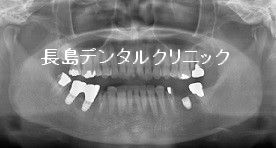

左下ブリッジを支えている2つの歯がそれぞれ虫歯になり再治療しブリッジにするのではなくインプラントを埋入した症例

1、インプラント埋入前

左下奥歯のブリッジを支えている左右の歯が虫歯になり、ブリッジを

外すことになりました。ブリッジは入れ歯と異なり取り外し式ではな

く慣れてしまえば自分の歯と同じように違和感なく噛むことができる

ようになります。ただブリッジを支える歯が神経を除去している場合

には歯の中に(通常では)金属の土台が使用されます。これは神経を

取らざるをえないような場合には虫歯が大きいのでその失った歯の

部分を金属で置き換える必要があります。そのために歯が割れやすく

なったり、虫歯になっても気が付かないので保存できないような状況

になります。またその部分の日々の清掃も通常の歯とは異なりますの

で歯ブラシだけでは十分な清掃ができません。そのためにもメンテナ

んスが大切です。